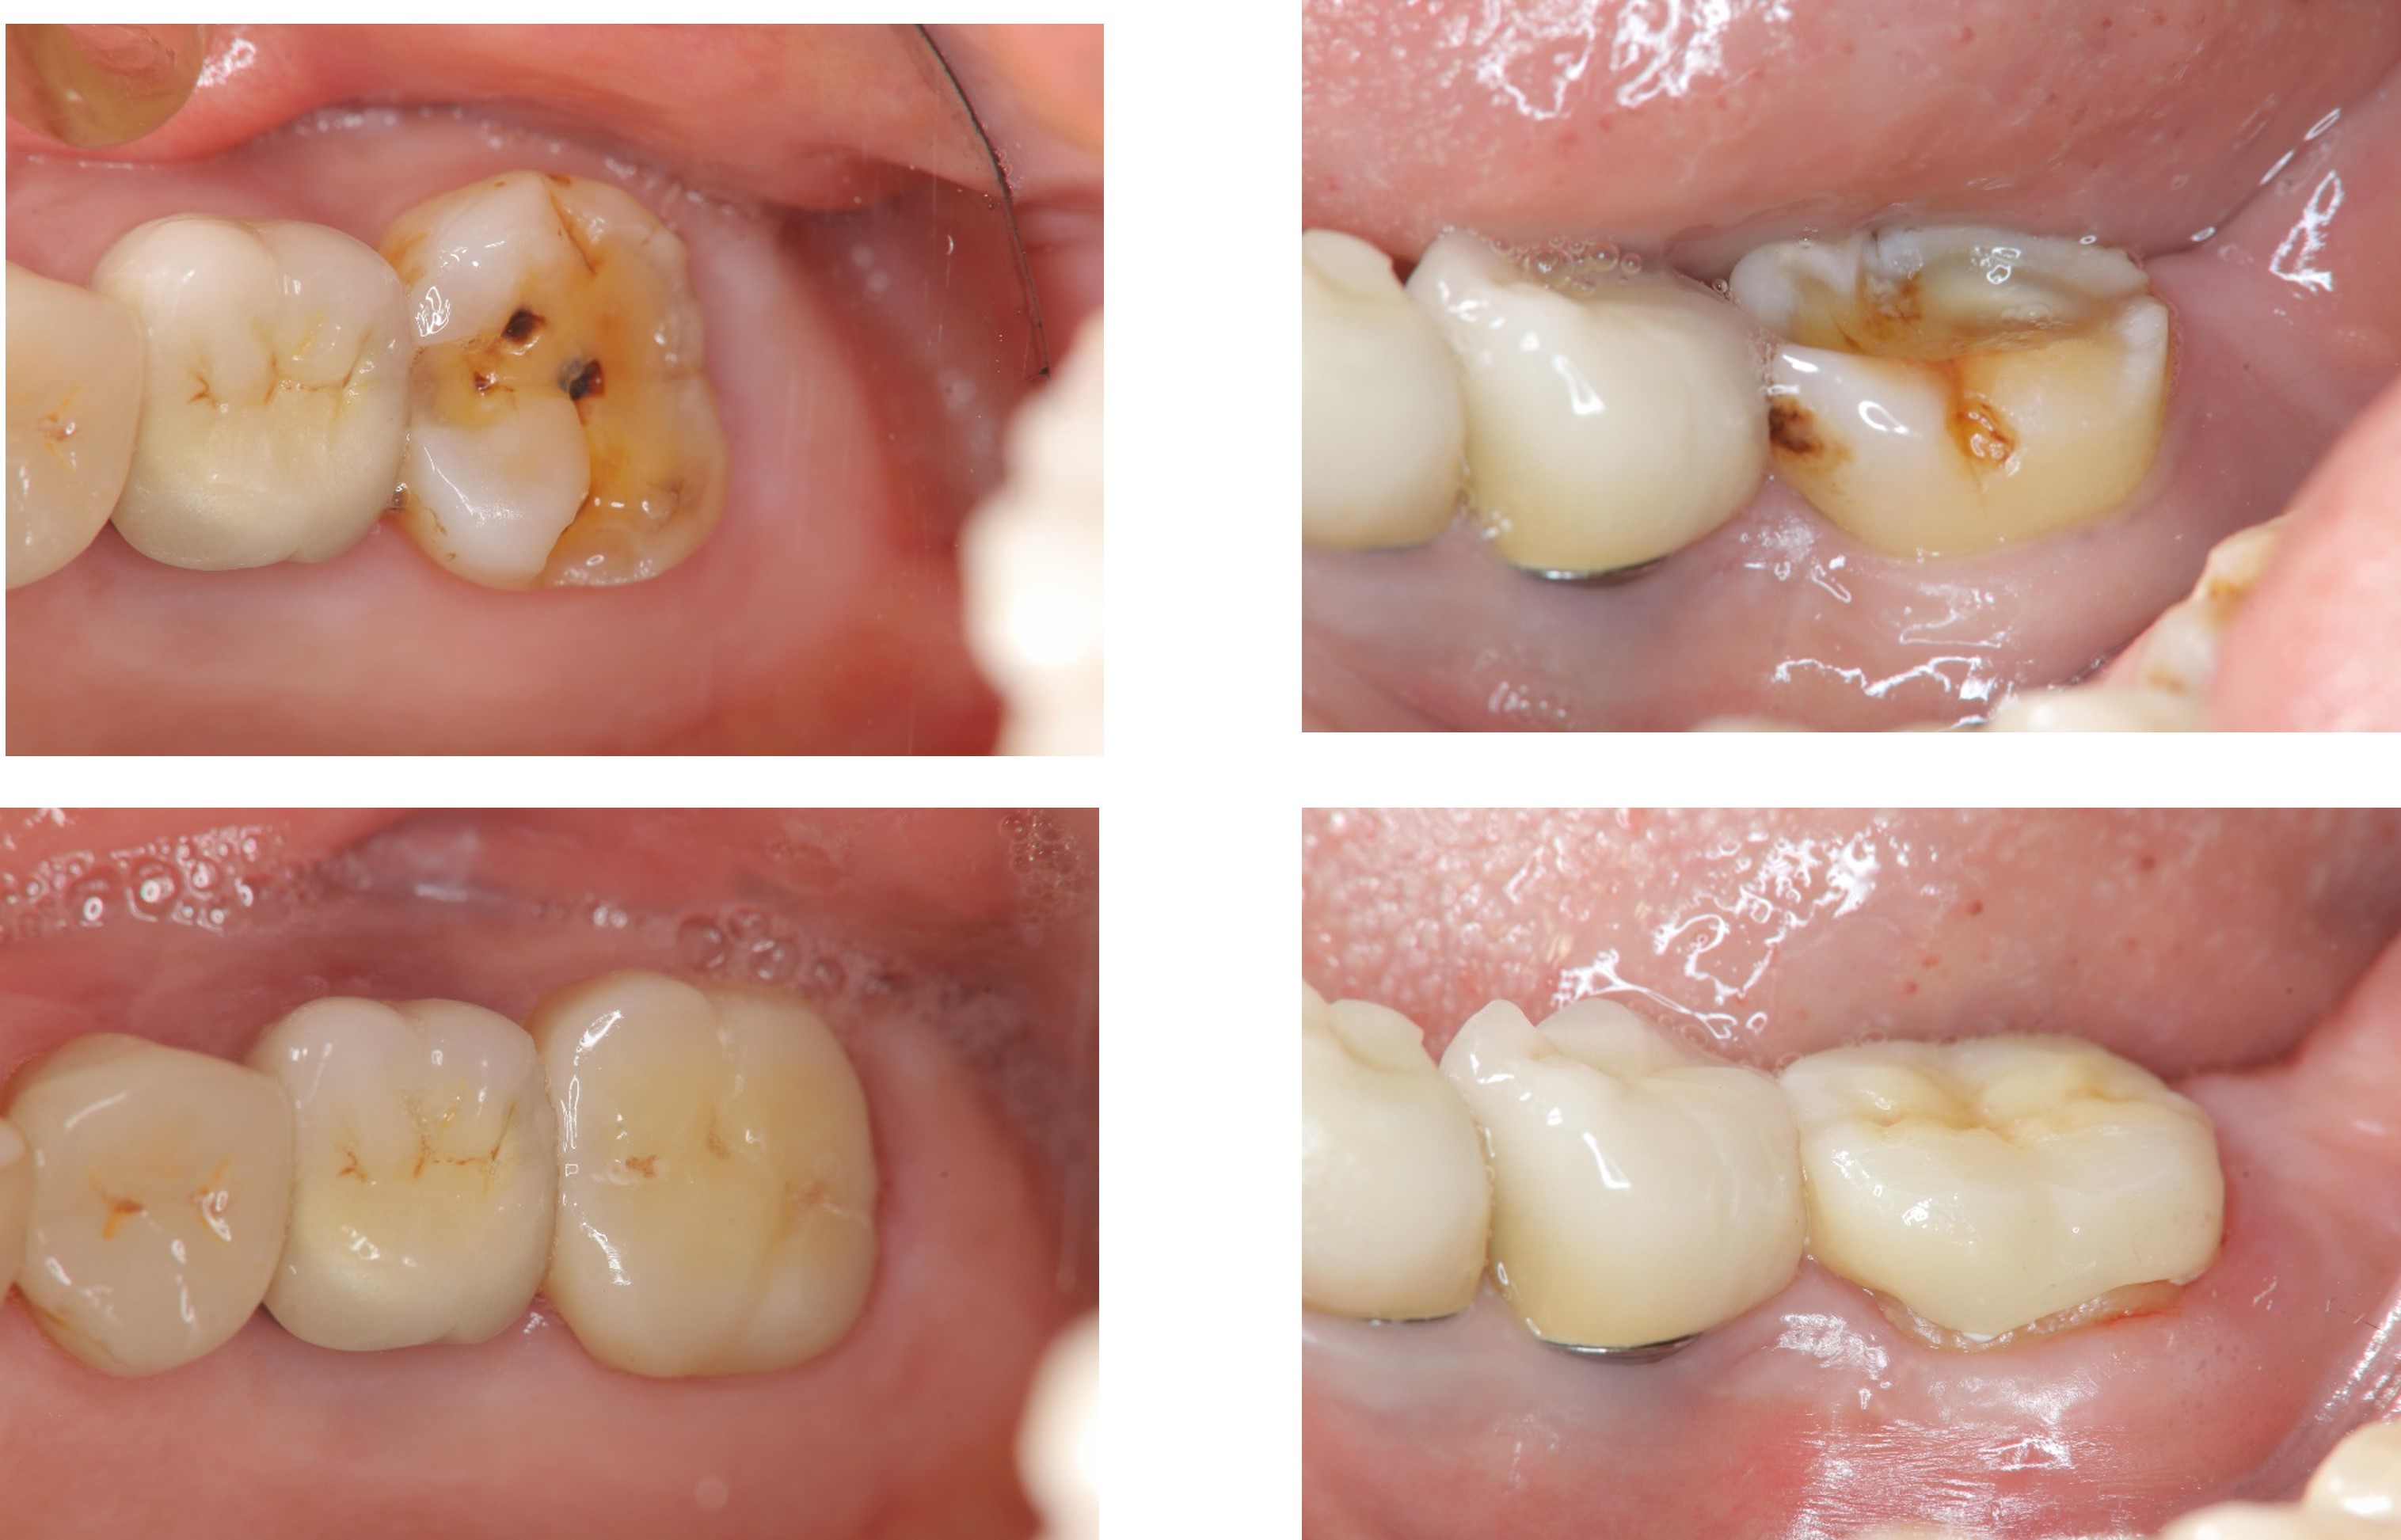

陶瓷冠蓋體-二次蛀牙-#46

審美牙科

瓷塊-冠蓋體